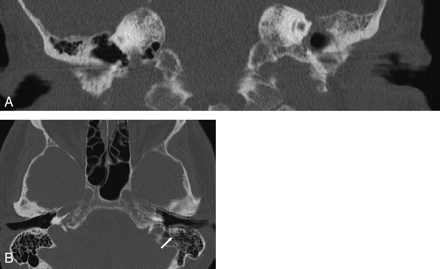

The evaluation of our examinations showed no moving artifacts in the SST scans, whereas the image quality of MSCT was decreased due to patients' moving in 2 cases (Fig 6). Nevertheless, in both cases, image quality was sufficient to establish a diagnosis; thus, the examinations did not need to be repeated.

MSCT of the temporal bone, coronal (A) and axial (B) MPR, section thickness 0.8 mm. No moving artifacts are found in the SST scans, whereas the image quality of MSCT is decreased due to the patients moving in 2 cases (A and B). In 1 of those 2 individuals, the mastoid segment of the facial nerve canal (arrow) can barely be seen on the left side due to motion artifacts (B). However, image quality was sufficient to establish a diagnosis in both patients; thus, the examinations did not need to be repeated.